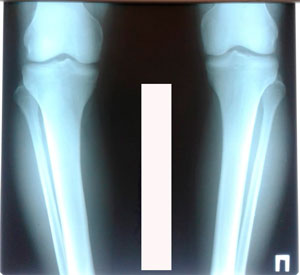

Исходник - 28 лет.

Дата операции - 27.02.2020

image-26-02-20-08-14-6.jpg

image-26-02-20-08-14-11.jpg